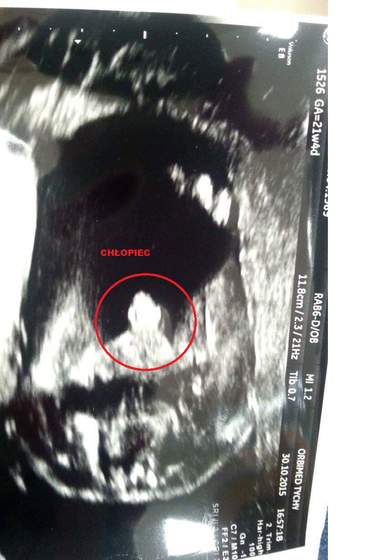

Tak jak pisałm kiedyś mój mąż to Grzesiu i urodził się 60 cm i 4150 g

I do dzisiaj kawał z niego chłopa